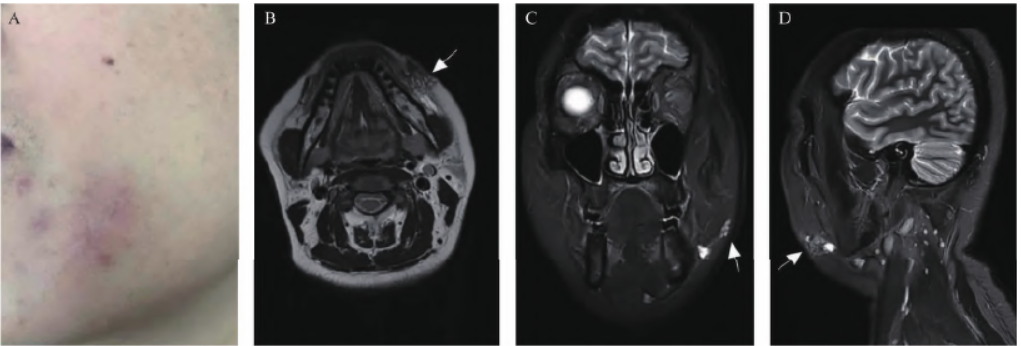

2023 年5 月再次就诊于北京协和医院,免疫组织化学检测结果:NTRK(+),结合综合形态、免疫组织化学检测结果及北京大学口腔医院多项FISH结果,考虑为NTRK 重排梭形细胞肿瘤。2023 年6 月于我院复查,患者自述术后未出现面神经损伤症状,因此未接受其他治疗;左侧面部术区可扪及一大小约1.0 cm×0.5 cm 肿块( 图5A ),复查颌面部增强MRI 示:左侧颌面部术后,术区多发小斑片强化影( 图5B —5D)。患者未行特殊治疗,回家继续观察。

图5 复查面部照片及影像学检查结果。A. 术后3 个月左侧面部术后照;B. 横断位;C. 冠状位;D. 矢状位。箭头示病变处。